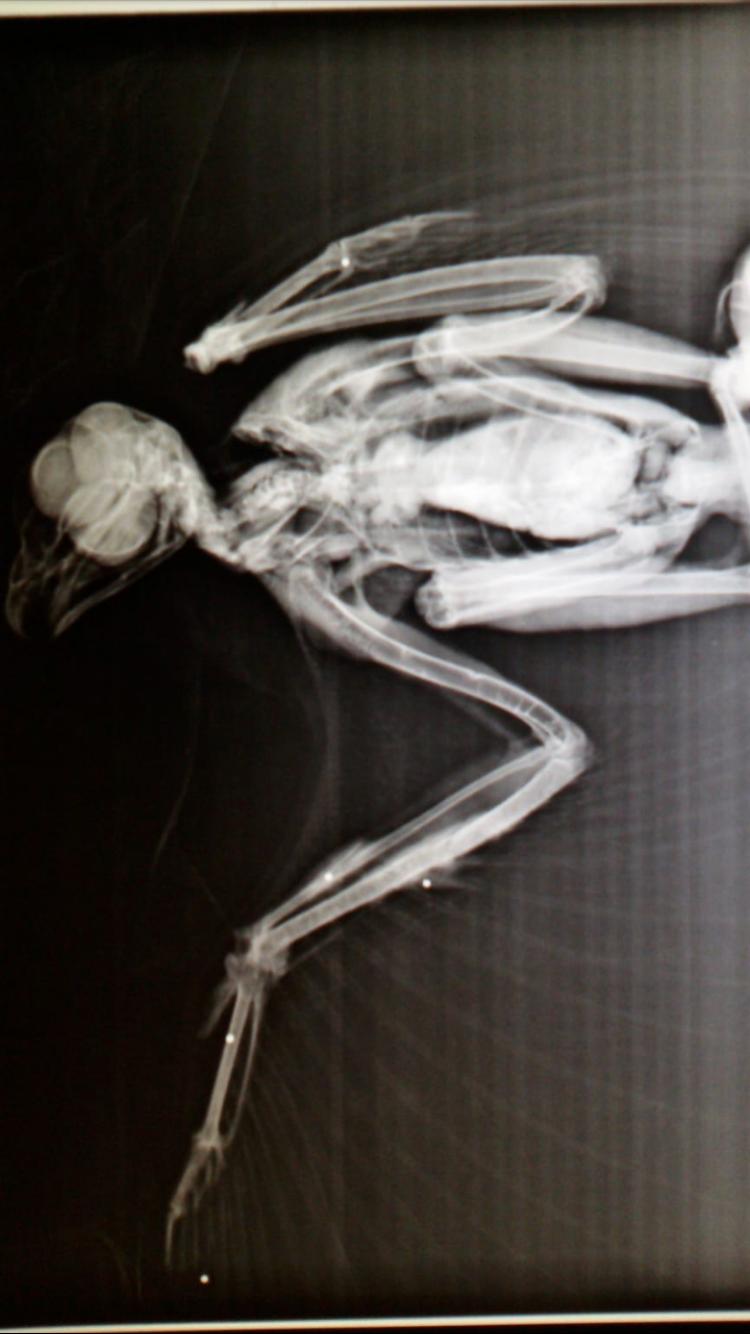

La radiografia effettuata sul corpo del volatile

Dalle prime analisi è emerso che la poiana è stata impallinata a causa di un atto di bracconaggio. Sono stati ritrovati quattro pallini di piombo nell’ala destra e un altro in quella sinistra. Tuttavia le fratture sono di lieve entità. Il secondo passaggio in seguito alle prime cure veterinarie sarà il trasferimento del rapace al Centro di recupero della fauna selvatica della Valpredina gestito dai volontari del WWF. Alle opere di recupero e salvataggio del volatile ha preso parte anche il sindaco Efrem Brambilla, che ha rivelato: «Al termine delle cure e una volta che sarà in grado di volare, la poiana verrà riportata a casa. Verrà nuovamente liberata e rilasciata a Santa Maria Hoè. Ci tengo a ringraziare tutta la famiglia Dozio (Maurizio, Mariella, Michael, Giada e Serena) per la pronta segnalazione. Il loro è stato un comportamento esemplare. Un ringraziamento speciale va anche all’agente Marco Ranaglia del Nucleo Faunistico Provinciale per la collaborazione e la tempestività nell’intervento».